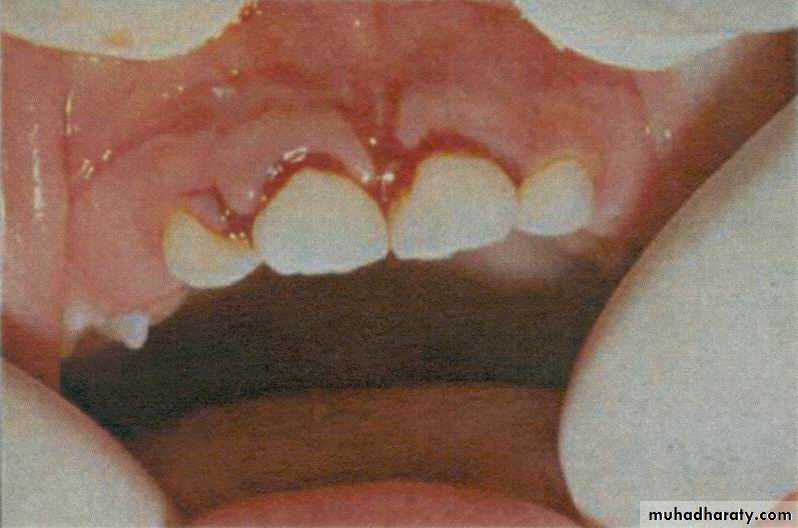

Diagnosis;

tooth is displacedcrown may be palatal or labially

displaced ;

not mobile nor tender

Radiology; PDL space is increased

and the apex is displaced

labially or palatally

Note labially displaced crown